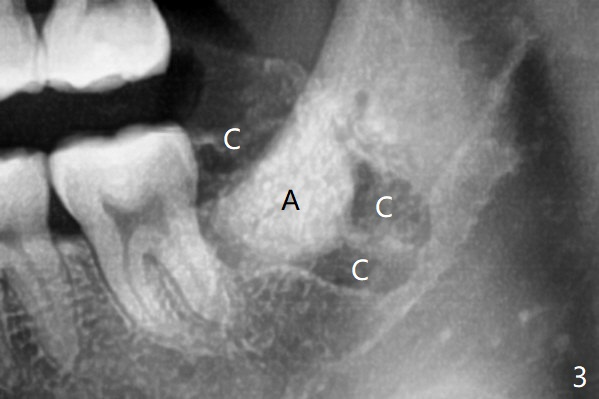

A: Bond Apatite; C: collagen plug.

Midbuccal Incision     Last     Next

Xin Wei, DDS, PhD, MS 1st edition 06/24/2020, last revision 06/25/2020